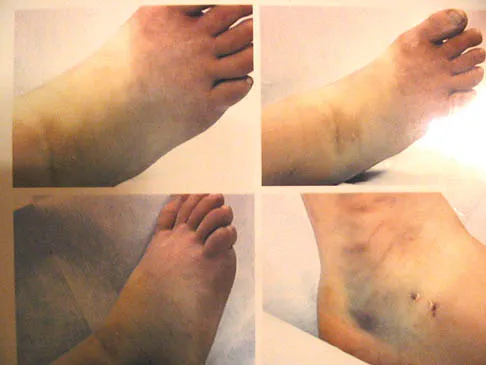

A 31-year-old woman has a history of a painful ankle that has failed to respond to conservative management. She has associated night pain that is relieved with nonsteroidal anti-inflammatory drugs. MRI and technetium Tc 99m scans are consistent with an osteoid osteoma. Management should now consist of

Explanation